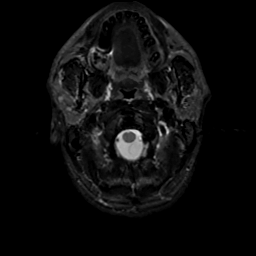

MR Study #16, June 23, 1991 -- Slice #1